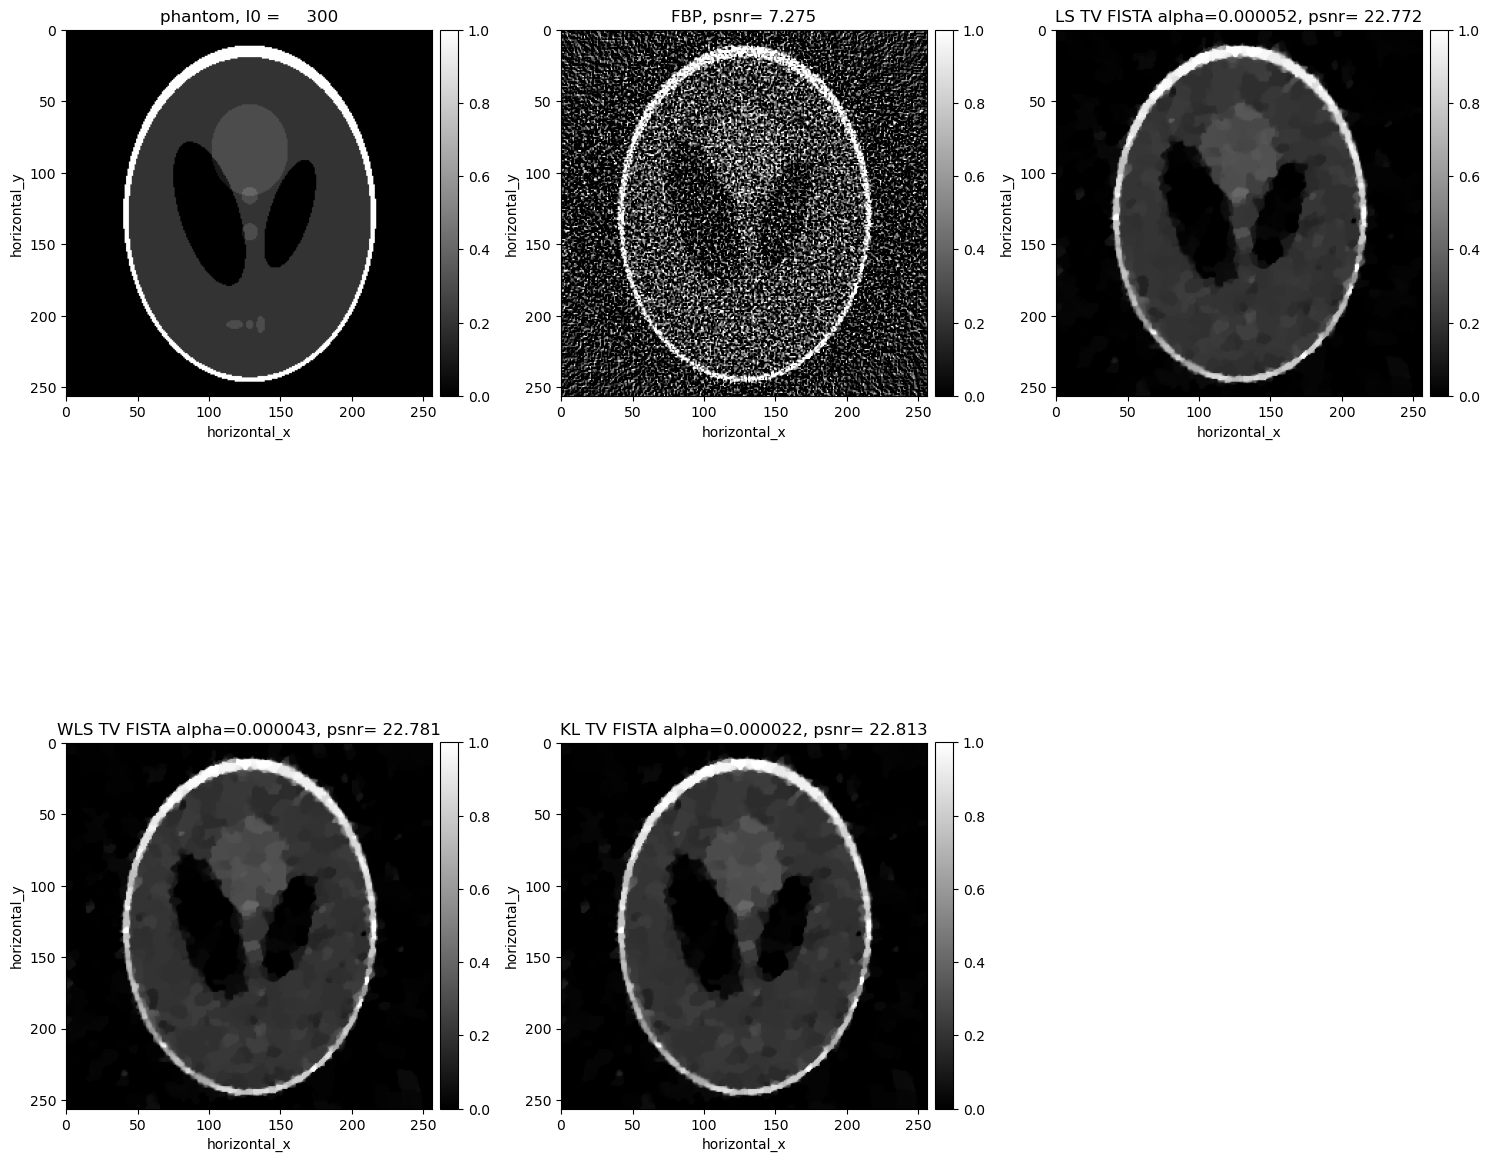

Comparisons without regularisation#

[21]:

show2D([phantom, recon_fbp, recon_ls,recon_wls, recon_kl ], ["phantom, I0 = %7.0f" % (background_counts), "FBP, psnr= %5.3f" % (psnr_fbp),\ "LS psnr= %5.3f" % (psnr_ls),\ "WLS psnr= %5.3f" % (psnr_wls), \ "KL psnr= %5.3f" % (psnr_kl)], \ cmap=cmap, fix_range =(0,1), num_cols=3, origin='upper-left')

../../_images/demos_LS_WLS_KL_TotalVariation_31_0.png

The KL reconstruction is better than the WLS reconstruction which is better than the LS reconstruction. However, all the above reconstructions are worse than the FDK reconcstruction and seem to be overfitting to the noise. In the next section, we consider reconstructions with TV regularisation.

Comparisons with TV#

[37]:

show2D([phantom, recon_fbp, recon_ls_tv_fista,recon_wls_tv_fista, recon_kl_tv_fista ], ["phantom, I0 = %7.0f" % (background_counts), "FBP, psnr= %5.3f" % (psnr_fbp),\ "LS TV FISTA alpha=%7.6f, psnr= %5.3f" % (alpha_ls_tv_fista,psnr_ls_tv_fista),\ "WLS TV FISTA alpha=%7.6f, psnr= %5.3f" % (alpha_wls_tv_fista,psnr_wls_tv_fista), \ "KL TV FISTA alpha=%7.6f, psnr= %5.3f" % (alpha_kl_tv_fista,psnr_kl_tv_fista)], \ cmap=cmap, fix_range =(0,1), num_cols=3, origin='upper-left')

../../_images/demos_LS_WLS_KL_TotalVariation_55_0.png